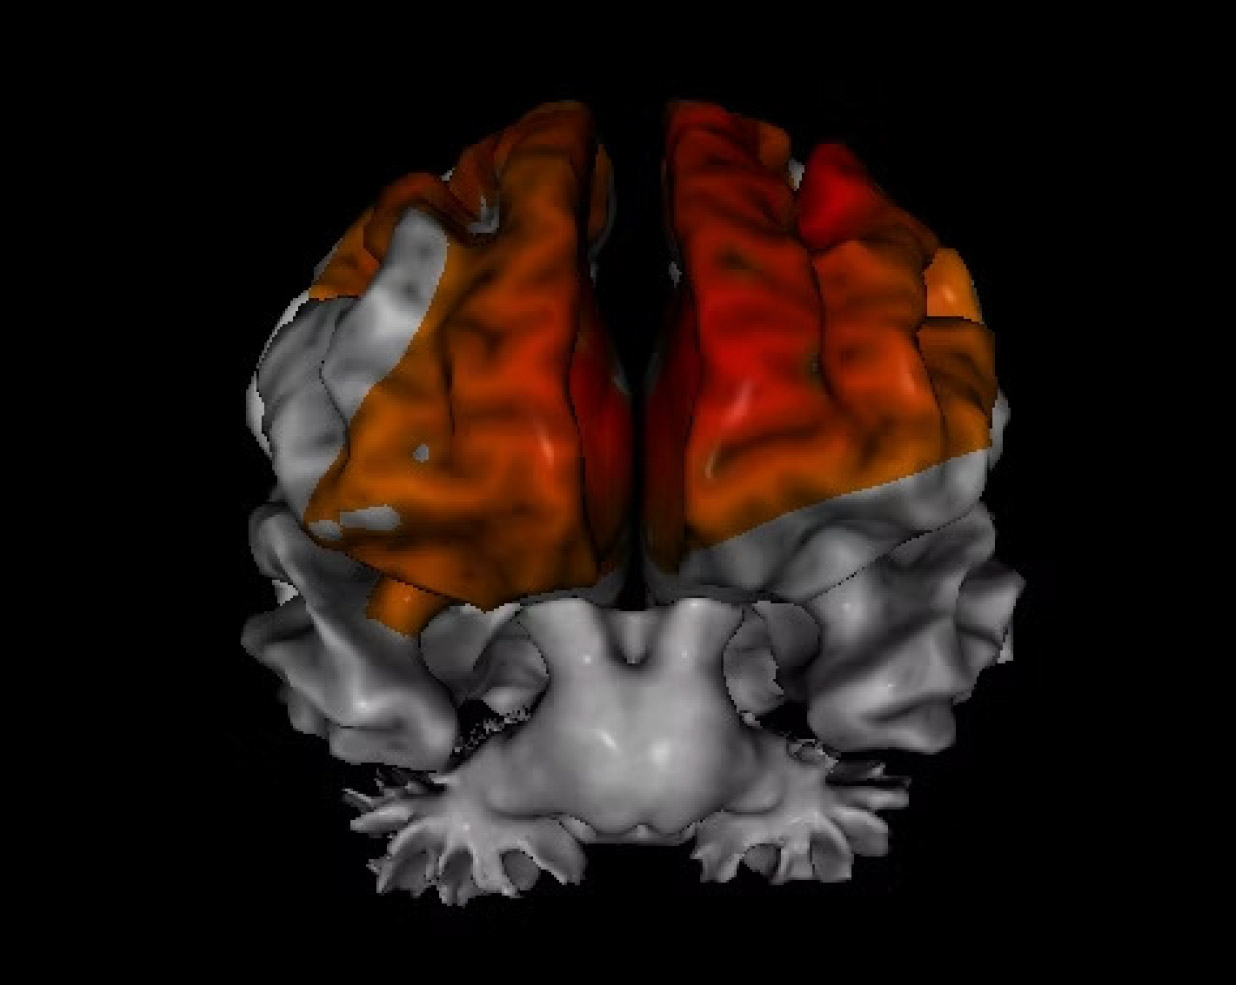

Source-localized electroencephalography (sLORETA) is a neuroimaging

technique that uses EEG data to localize the source of brain activity in specific

regions. It helps us understand the underlying neural roots of symptoms and

specific areas of dysfunction.

This neuroimaging can also assist with determining the most effective treatment

interventions, including which medications and/or supplements could be

beneficial, as well as neurotherapy protocols and other interventions designed to

improve functioning within regions showing impairment.